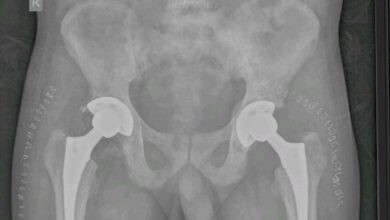

मेकाहारा में सिकल सेल पीड़ित मरीज के कूल्हे की हड्डी का सफल प्रत्यारोपण

रायपुर । पंडित जवाहर लाल नेहरू स्मृति चिकित्सा महाविद्यालय रायपुर से संबद्ध डॉ. भीमराव अम्बेडकर स्मृति चिकित्सालय के अस्थि रोग…